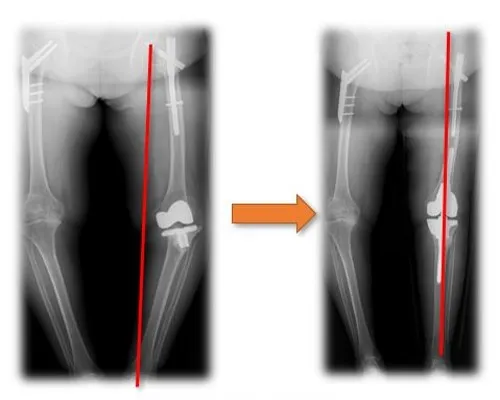

Hip Dysplasia Replacement 1

Hip Dysplasia Replacement 2